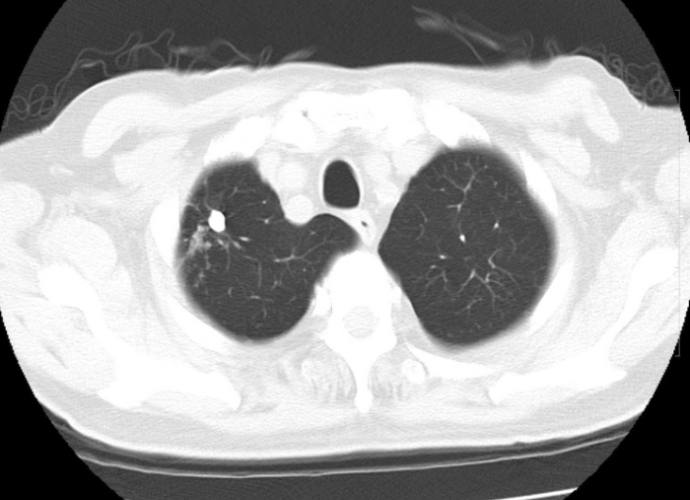

肺結節,說白了就是在肺部影像上(通常是電腦斷層掃描,CT)看到的一個小點點、小團塊。聽我說,這個小點的定義非常重要:它必須是圓的或類圓的,邊界相對清晰,而且直徑小於或等於3公分。如果大於3公分,我們就不叫它肺結節了,我們稱之為「腫塊」,性質和處理方式會很不一樣。所以下次聽到肺結節,心裡要有個概念:大小是個關鍵指標。這個「肺結節知識」是理解後續所有問題的基礎。

最常見的就是胸部X光片和胸部電腦斷層掃描(CT)。胸部X光相對便宜、輻射低,但有它的限制,比較小的結節或者位置刁鑽的被肋骨擋住的結節,X光可能就看不到了。現在很多健康檢查會納入低劑量電腦斷層(LDCT)篩檢早期肺癌,它的靈敏度高太多了,1-2毫米的小點點都能抓出來。很多原本X光看不到的肺結節,一做LDCT就無所遁形,這也是為什麼感覺「肺結節」變多了的原因之一。這點「肺結節知識」能幫助大家理解為何近年來診斷率提高。

磨玻璃樣肺結節(GGO)特別在哪?